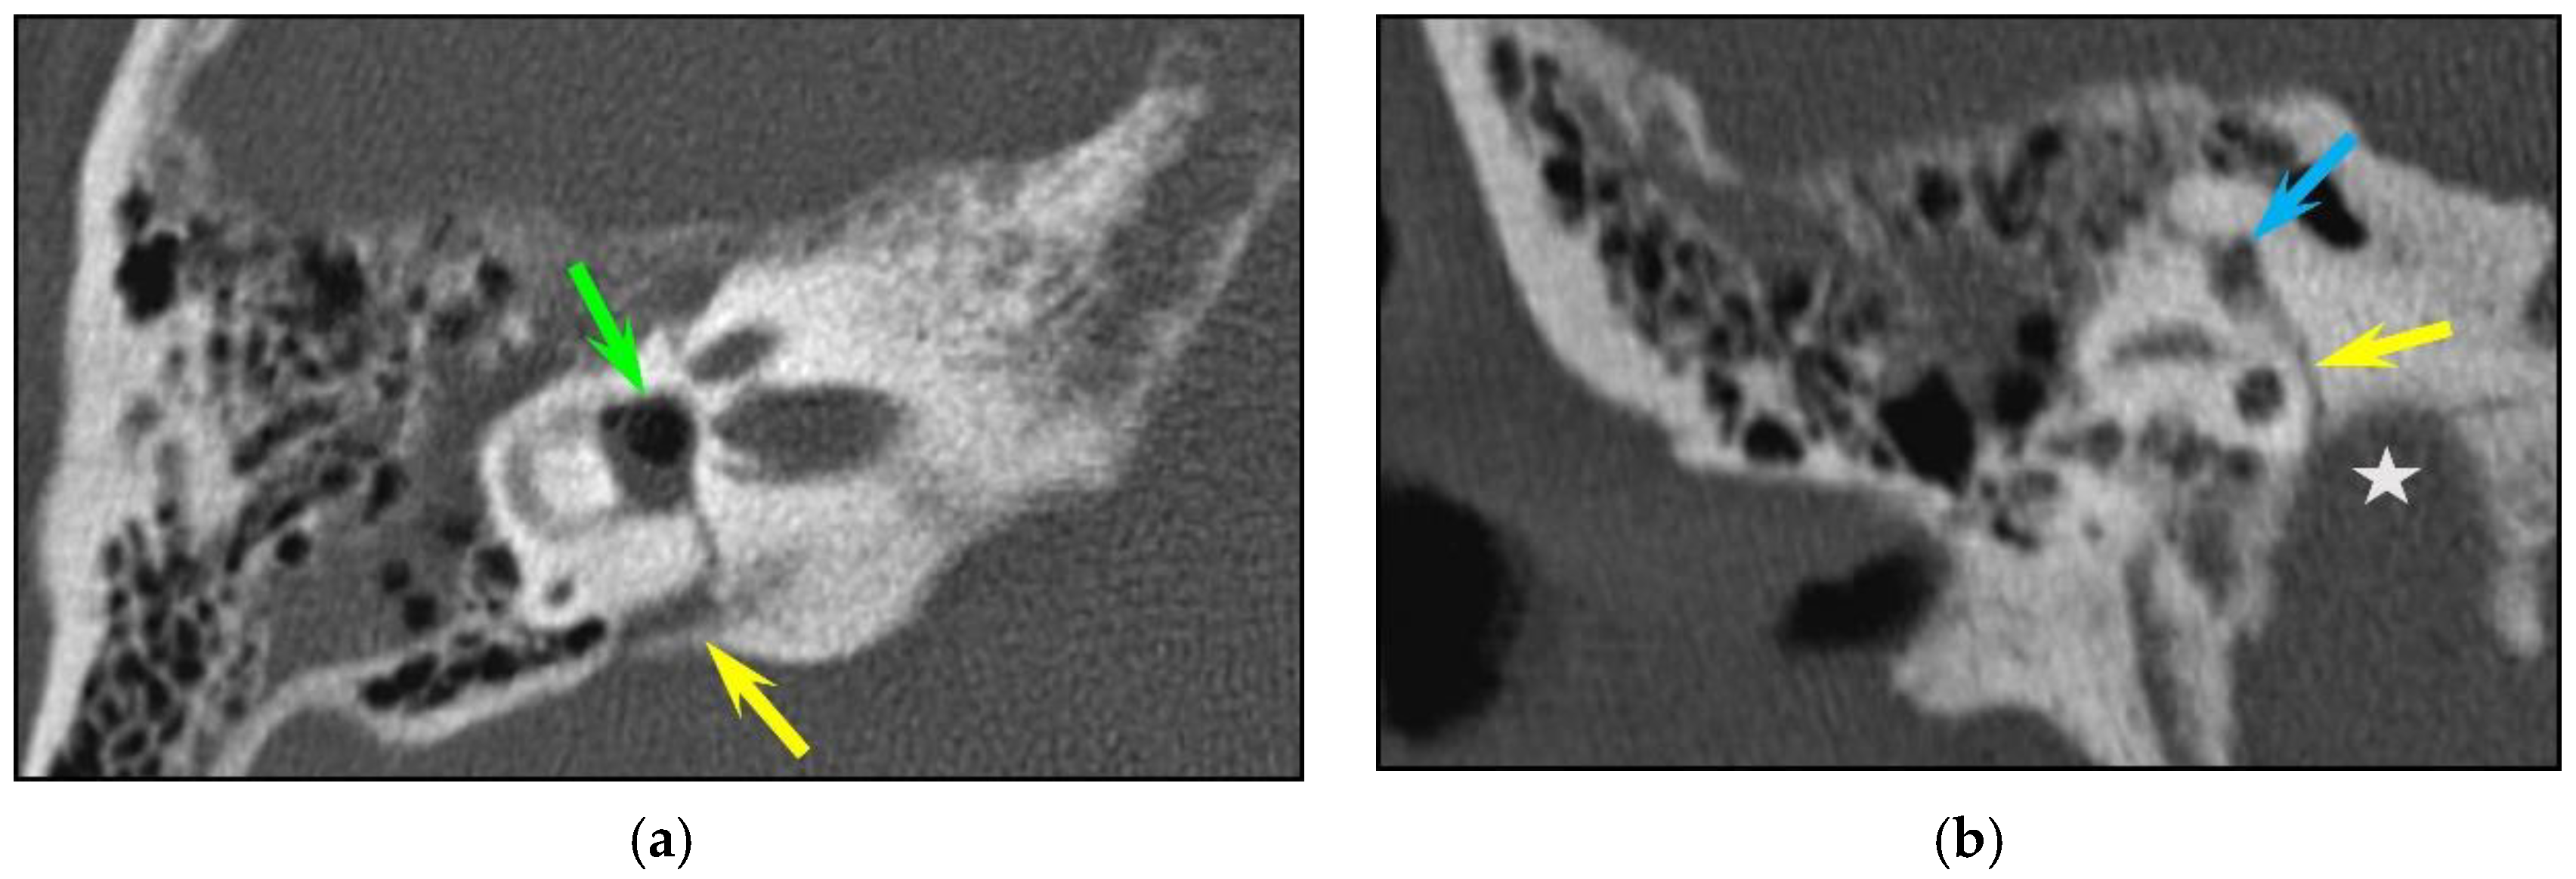

Figure 2. Facial canal injuries. Fracture of the left temporal bone in a 25-year-old man with peripheral facial palsy after a fall. CT of the left temporal bone: longitudinal fracture (yellow arrow) with associated bony fragments in the geniculate ganglion fossa (green arrow) consistent with a geniculate facial canal injury.

In total, fractures involved the bony labyrinth in 11 cases and extended into the following structures: semi-circular canals (posterior semi-circular canal, n = 3; superior semi-circular canal, n = 2), vestibule (n = 3), cochlea (n = 1) and the vestibular aqueduct (n = 2). Involvement of the internal auditory canal was seen in two cases. Fracture lines extended into the petrous apex in 10/126 (7.9%) of all temporal bone fractures, and fractures along the osseous structures surrounding the facial nerve were seen in 8/126 (6.3%) cases. The fractures lines involved the geniculate fossa in four cases (Figure 2), the facial nerve canal in the tympanic cavity in two cases and the bony structure surrounding the second genu of the facial nerve in two cases, respectively. Air in the tympanic facial canal without a visible fracture line was present in one case.

Facial nerve palsy is a major clinical concern in the event of temporal bone fracture, and it has been reported to occur in about 7–10% of fractures. In most cases, the onset of facial nerve palsy is immediate; however, in a minority of cases, facial nerve palsy may present with delayed onset (after 5 days) due to inflammation and swelling compressing the facial nerve. In our study, radiologically detected injuries of the facial canal and the osseous boundaries of the other facial nerve segments were present in eight cases, most often in the region of the geniculate ganglion; however, facial palsy was present or developed later in only four cases. The incidence of facial nerve palsy was, therefore, very low (only 3%), which is in contradiction to other data from the literature, in which the reported incidence of complete facial palsy is quite high: 25% in longitudinal fractures and 44% in transverse fractures, respectively [11]. In some cases, patients develop facial palsy without a visible fracture line, as in one of our cases, in which only a tiny air bubble was present in the facial canal. It is therefore possible that some fractures are not detectable with a standard CT protocol, as conducted in an emergency setting. In these cases, additional evaluation with a dedicated high-resolution CT scan of the temporal bone is indicated if decompression of the facial canal is planned in case of post-traumatic facial nerve palsy [30,31].